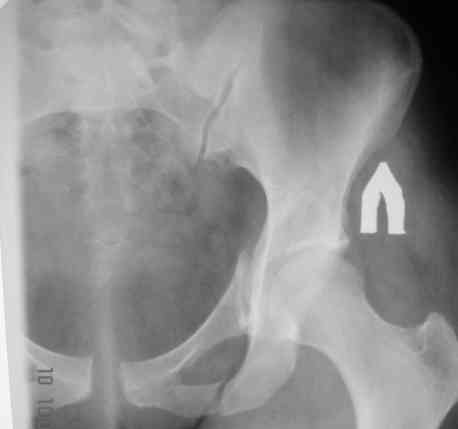

В больнице вправили вывих бедра, три недели на вытяжении. Беспокоят боли в левом тазобедренном суставе и левом крестцово-подвздошном сочленении. Ходит с тростью. Снимок - в приложении. Направил на КТ, заключение: разрыв симфиза и левого крестцово-подвздошного сочленения, переломы крыши и заднего края вертлужной впадины, горизонтальной ветви лонной кости слева.

Уважаемый д-р Булахтин, на мой взгляд единственное повреждение требующее синтеза - застарелый разрыв лона. Низкий перелом передней колонны безопасен, повреждения свода не вижу, неясно что было сзади (скорее боковая масса)лучше сделать обзорный снимок прямой и Inlet.

Очень похоже на повреждение от бокового сжатия.

Признаков разрыва сочленения не вижу, м.б. контрлатеральный перелом боковой массы.

Если был задний вывих, то повреждение должно локализоваться сзади. В данном случае перелом спереди, как результат сдавления лонного сочленения.